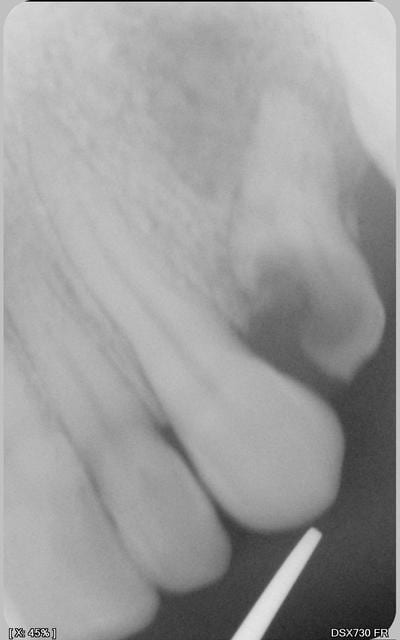

Hors la has recommande la cotation de clichés rétro coronaires au niveau molaire et prémolaire je cite " en l'absence d'une situation clinique spécifique" donc en prévention je suppose. quelle est leur cotation ? 1 à 3 dents contiguës comme les rétro alvéolaires ? ou que dalle ? Au niveau incisif pas de radio nécessaire les caries pouvant etre détectables aisément selon le guide de bonnes pratiques.

Personnellement, à chaque bilan annuel, c'est détartrage et 2 BW (un à droite, et un à gauche), donc Z12, et avec ça, j'ai une bonne vue d'ensemble. Pas la peine de faire toutes les radios que tu fais!

LIBELLE : Radiographie intrabuccale rétroalvéolaire et/ou rétrocoronaire d'un secteur de 1 à 3 dents contigües

Tiens j'ai essayé le cliché rétro coronaire avec mon kodak 6100. Outre le fait que le patient est à 2 doigts de sectionner le cable en mordant, il est impossible d'avoir toutes les couronnes haut et bas de La 7 à la 4.

Excuses moi mais débutantes c'est une rétro alvéolaire (ou rétro coronaire) qu'il faut faire. C'est ce qu'on fait quand on a un pano en cas de doute , non ?

Effectivement les BW sont plus facilement réalisables avec une plaque phosphore genre Vistascan.

Quand je pense aux nombres de caries interproximales ou lésions apicales qu'on découvre fortuitement sur des rétros.....!

Je fais des rétros à chaque contrôle avec souvent un détartrage, et que cela soit ça ou pano, je vois mal comment on peut nous dire que cela n'est pas justifié?

Le patient vient faire sa visite annuelle, sans rétros je suis incapable de lui assurer que tout va bien....!